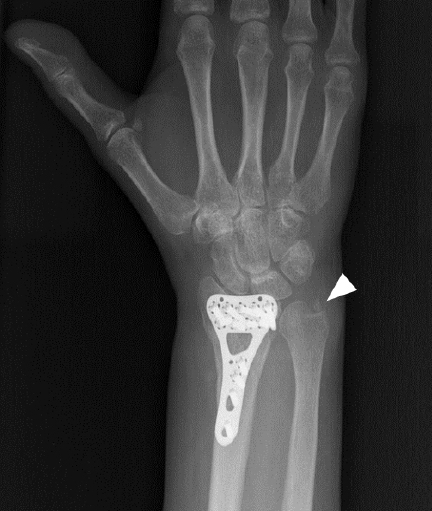

The second case involved a 54-year-old female with fractures of the distal radius and ulnar styloid process. She wore a cast for 5 weeks and then underwent internal fixation of the distal radius (Fig. 2). She later complained of pain/dysesthesia in the first three fingers of the right hand. Upon ultrasound examination, the median nerve and metallic plate were located close to each other on both short- and long-axis imaging (Supplementary Fig. 1). On dynamic ultrasound examination (Supplementary Videos 2, 3), the median nerve appeared to be very close to and intermittently irritated by the underlying metallic plate on the distal radius. The median nerve was much more compressed during wrist flexion/extension movements. Furthermore, the patient described pain/dysesthesia during the dynamic, real-time ultrasound examination. Again, the metallic plate was thought to be the direct cause of median nerve irritation. The patient had not undergone electrodiagnostic testing before. She was prescribed physical therapy (whirlpool and exercise).

Fig. 1.

Ultrasound imaging of the median nerve at the volar wrist. (A) Short-axis view depicts the close relationship between the bifid median nerve (white arrows) and the metal plate (arrowheads). (B) Long-axis view clearly shows the swollen median nerve (red vs. blue arrows) distal to compression (black arrow) by the underlying metal plate (arrowhead). Insets show the transducer’s position. ft, flexor tendon.